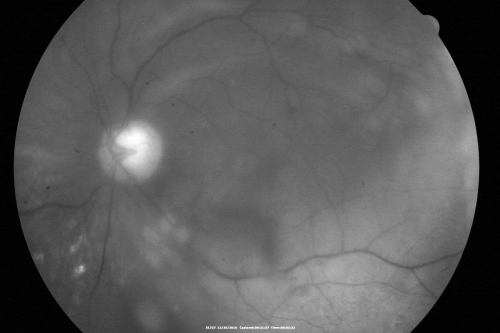

Proliferative Diabetic Retinopathy Both Eyes - Vitreous Hemorrahge Left Eye

67-year-old man has proliferative diabetic retinopathy in both eyes with vitreous hemorrhage in the left eye.  He has had pan retinal laser in the left eye.  The vitreous hemorrhage has been there for greater than two years and his vision is still hazy.  He takes Lumigan in both eyes for his glaucoma.

VISUAL ACUITY:  OD 20/40,  OS 20/40